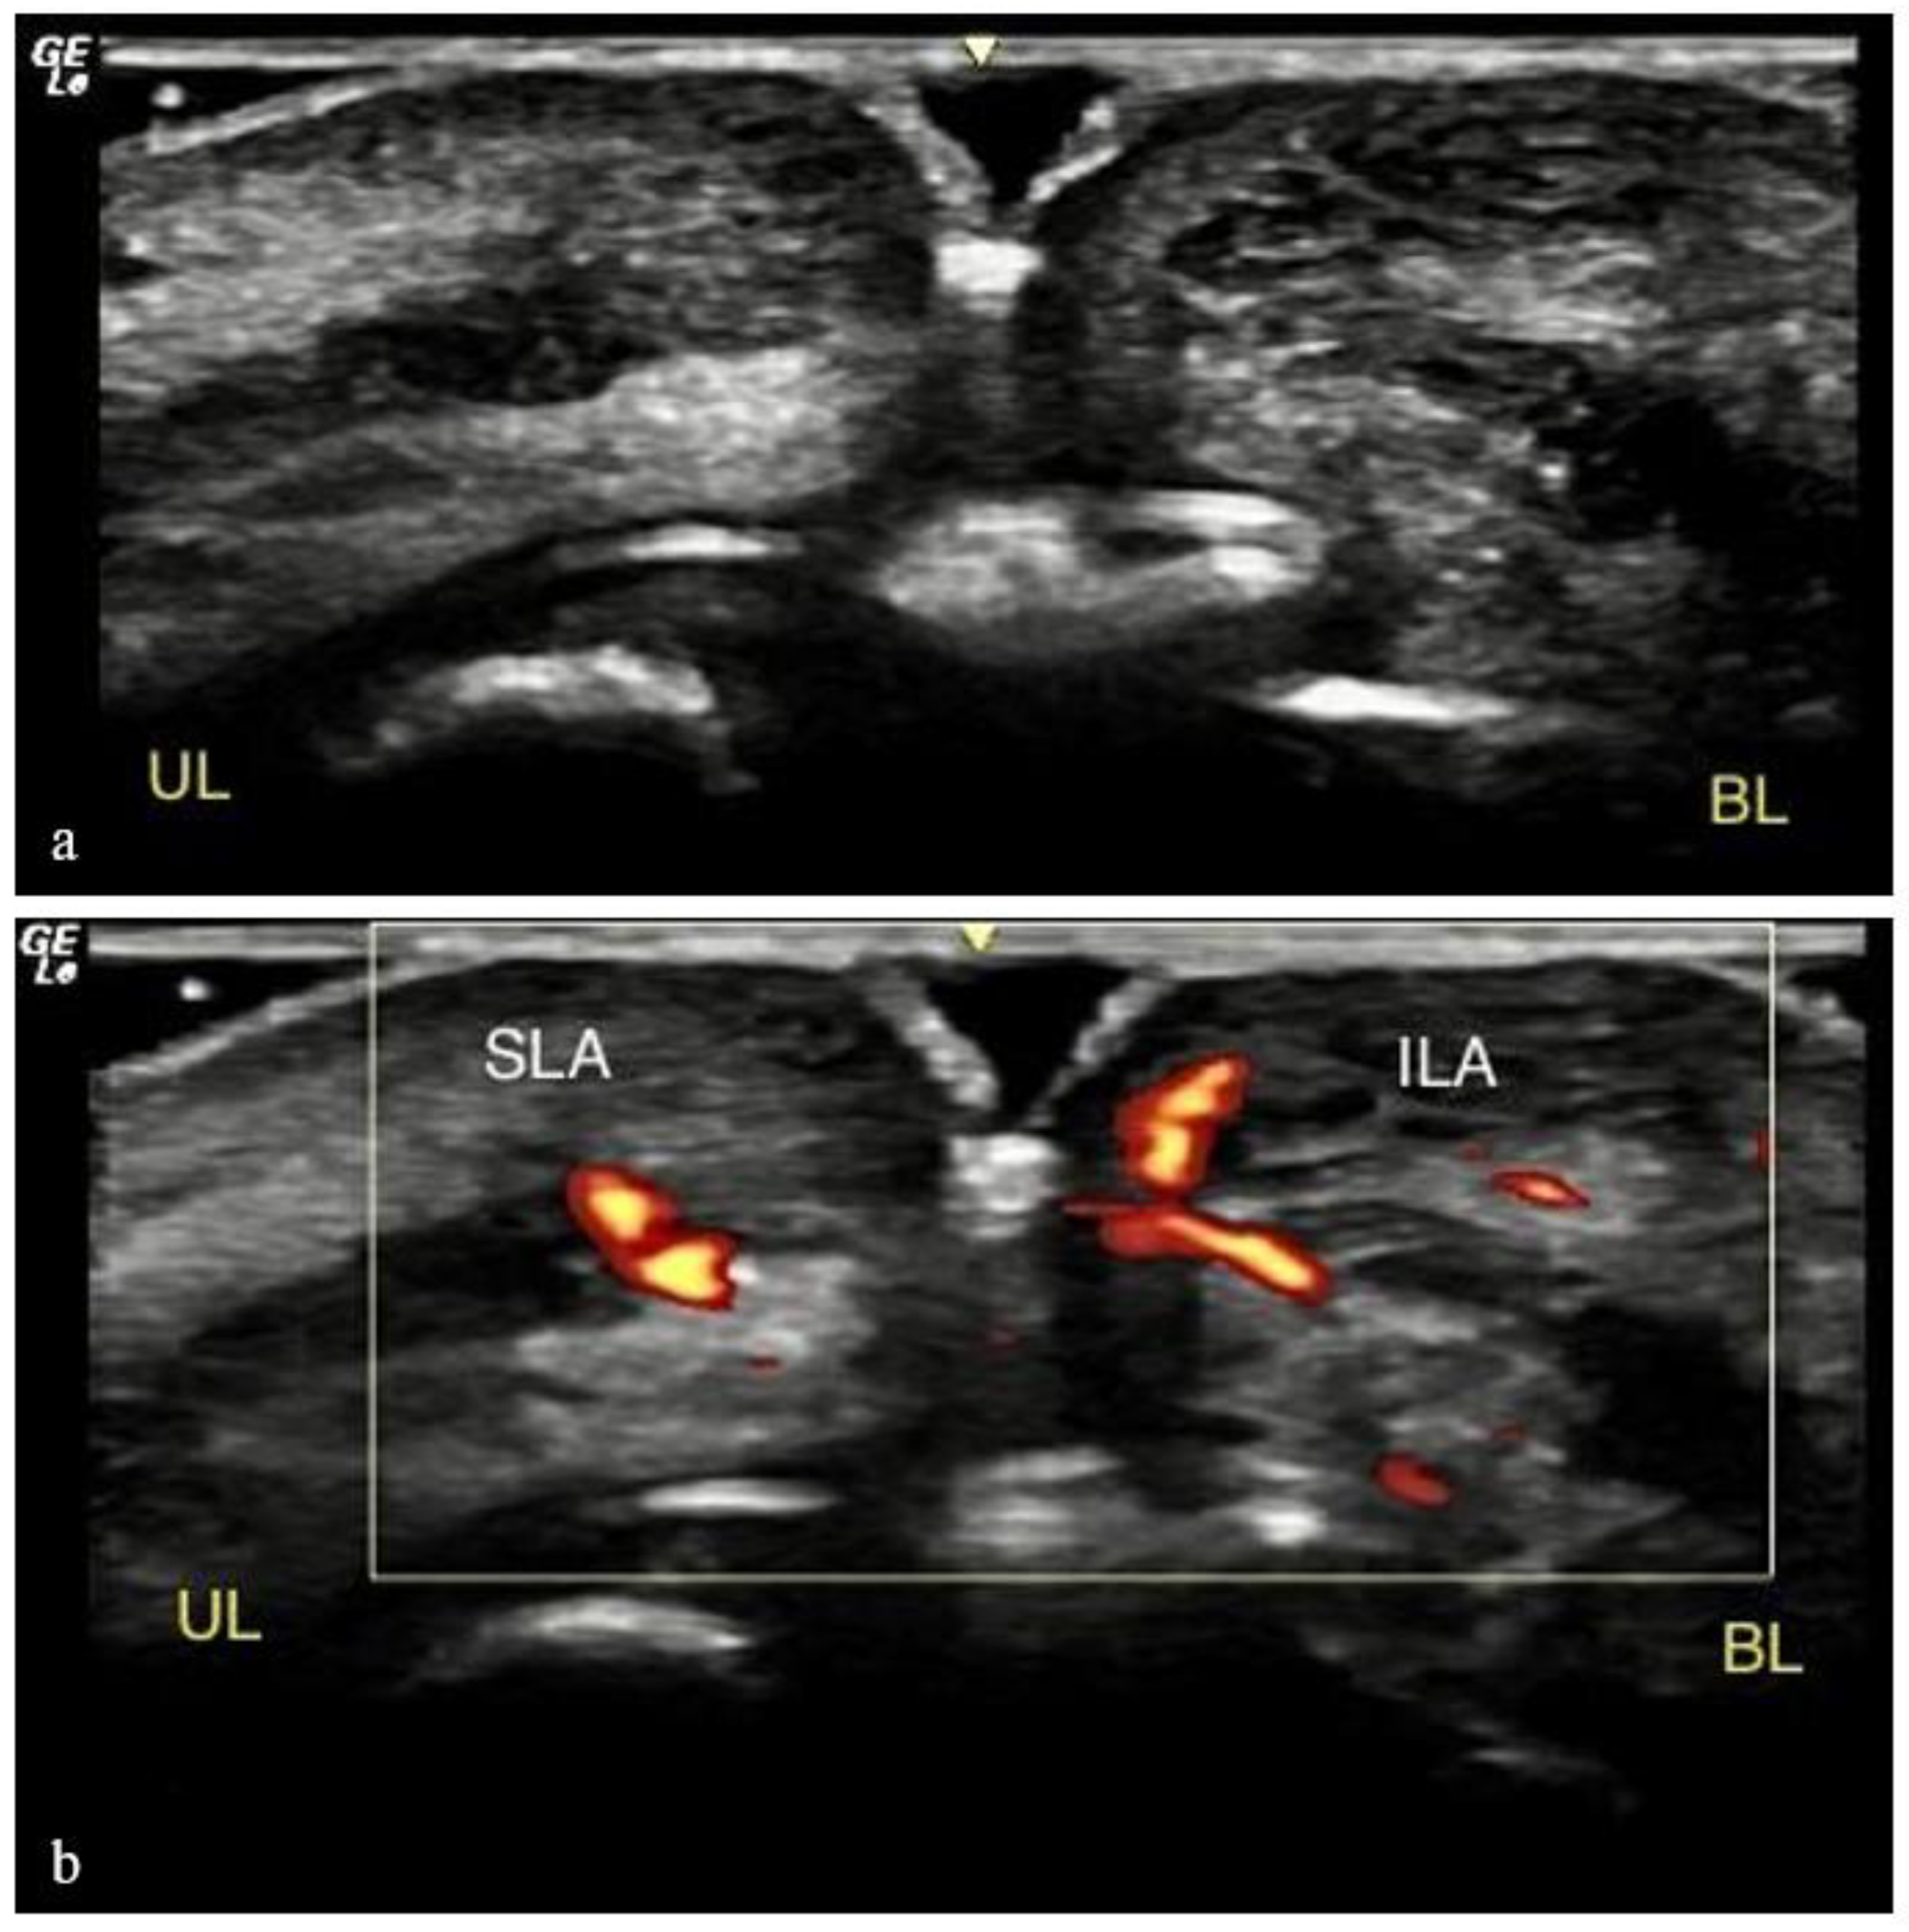

2.3. Ultrasound Analysis

- (i)

- (ii)